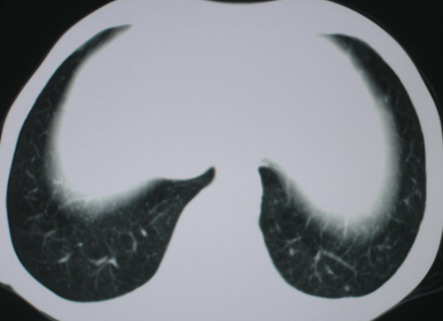

以下是引用医影拾贝在2008-6-3 18:48:00的发言:[br]双上肺弥漫性小结节影,纵隔窗内钙化淋巴结影,考虑血播性tb可能性较大,不除外肺ca可能

以下是引用卜一在2008-6-3 19:33:00的发言:[br]双肺结节,以双上肺分布为多,期间搀杂片状致密影及索条致密影。考虑:继发性肺结核伴血型播散可能性大。不除外肺泡ca的可能!另:椎体退变!

以下是引用panyishengct在2008-6-3 21:09:00的发言:[br]双上肺弥漫性小结节影,纵隔窗内钙化淋巴结影,考虑矽肺或/和tb可能性较大,不除外肺ca可能。腰椎考虑退变。 [br][br]